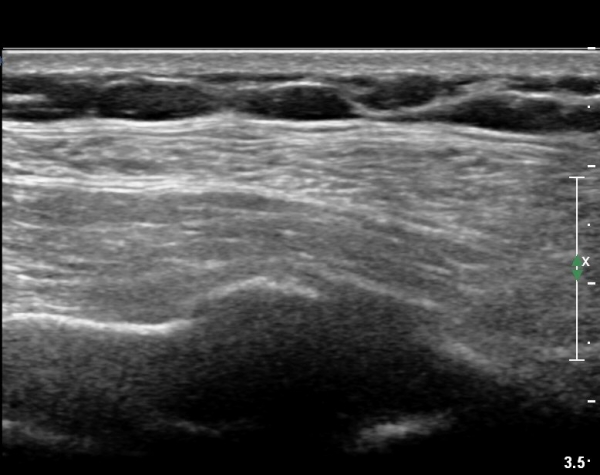

on moving of prove a little, there is bony protrusion(osteoblastic lesion) and hypoechoic(osteolytic)  lesion(image 2, 3, 4).

in transverse scan, visualization of osteoblastic mass with central osteolytic lesion(image 5, 6).

If there is no trauma history  or visualization of callus so ealry , doctor consider the possibility of tumors of rib.

As like this case, visualization of osteoblastic lesion and osteolytic lesion in simultaneously  suggests a malignant mass.